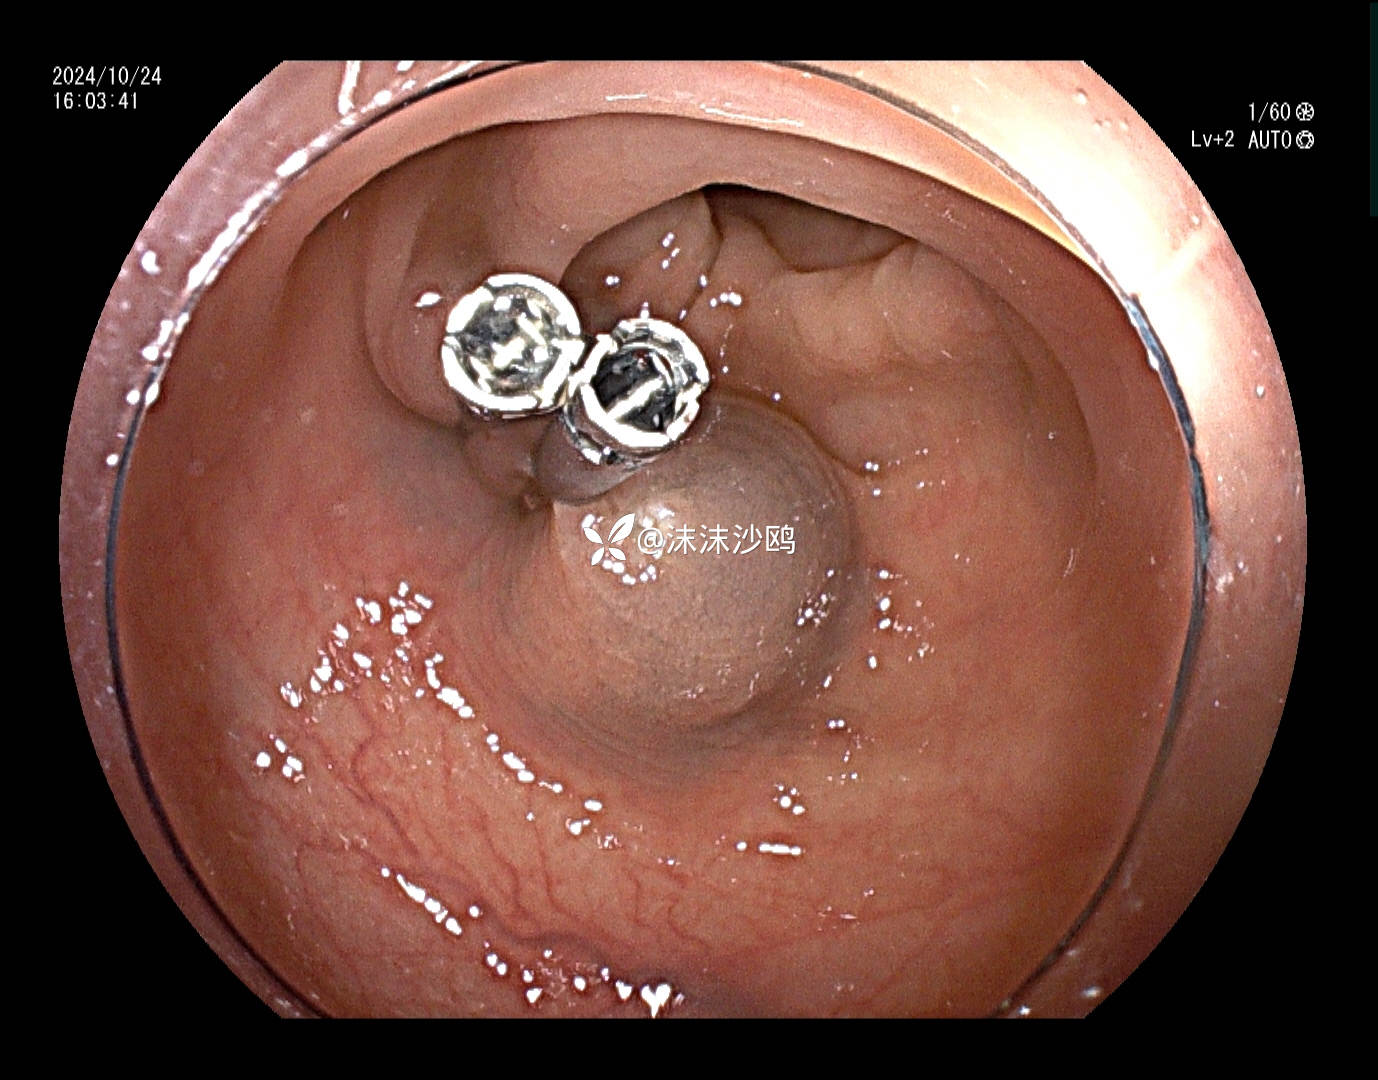

患者去年发现乙状结肠肿瘤同是发现多发腺瘤样隆起,先做了肿瘤切除手术,没有进一步放化疗,现来复查肠镜顺便嘎息肉。翻看之前的肠镜报告,肠道清洁差,发现的息肉就有六七个,应该还有漏掉的。嘱患者肠道一定要清洁到位。今日下午只安排了他一个人的肠镜专场,专门处理他的息肉。

冰山一角,大大小小嘎了十三四个,大的就有六七个,大部分EMR切除。希望术后不要有并发症。